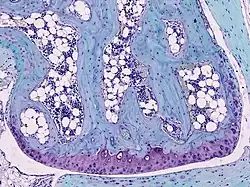

Light micrograph of undecalcified hyaline cartilage showing chondrocytes and organelles, lacunae and matrix.

Cartilage is composed of specialized cells called chondrocytes that produce a large amount of collagenous extracellular matrix, abundant ground substance that is rich in proteoglycan and elastin fibers. Cartilage is classified into three types — elastic cartilage, hyaline cartilage, and fibrocartilage — which differ in their relative amounts of collagen and proteoglycan.